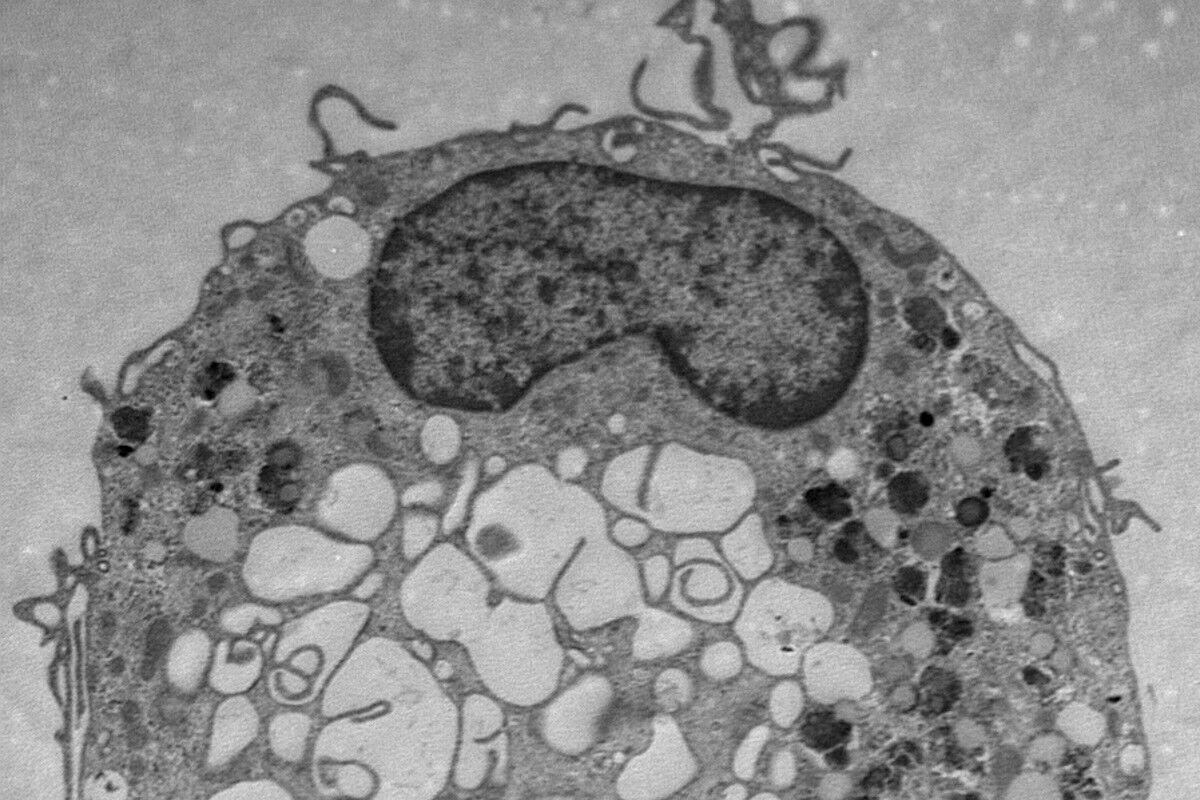

Une cellule vue au microsope